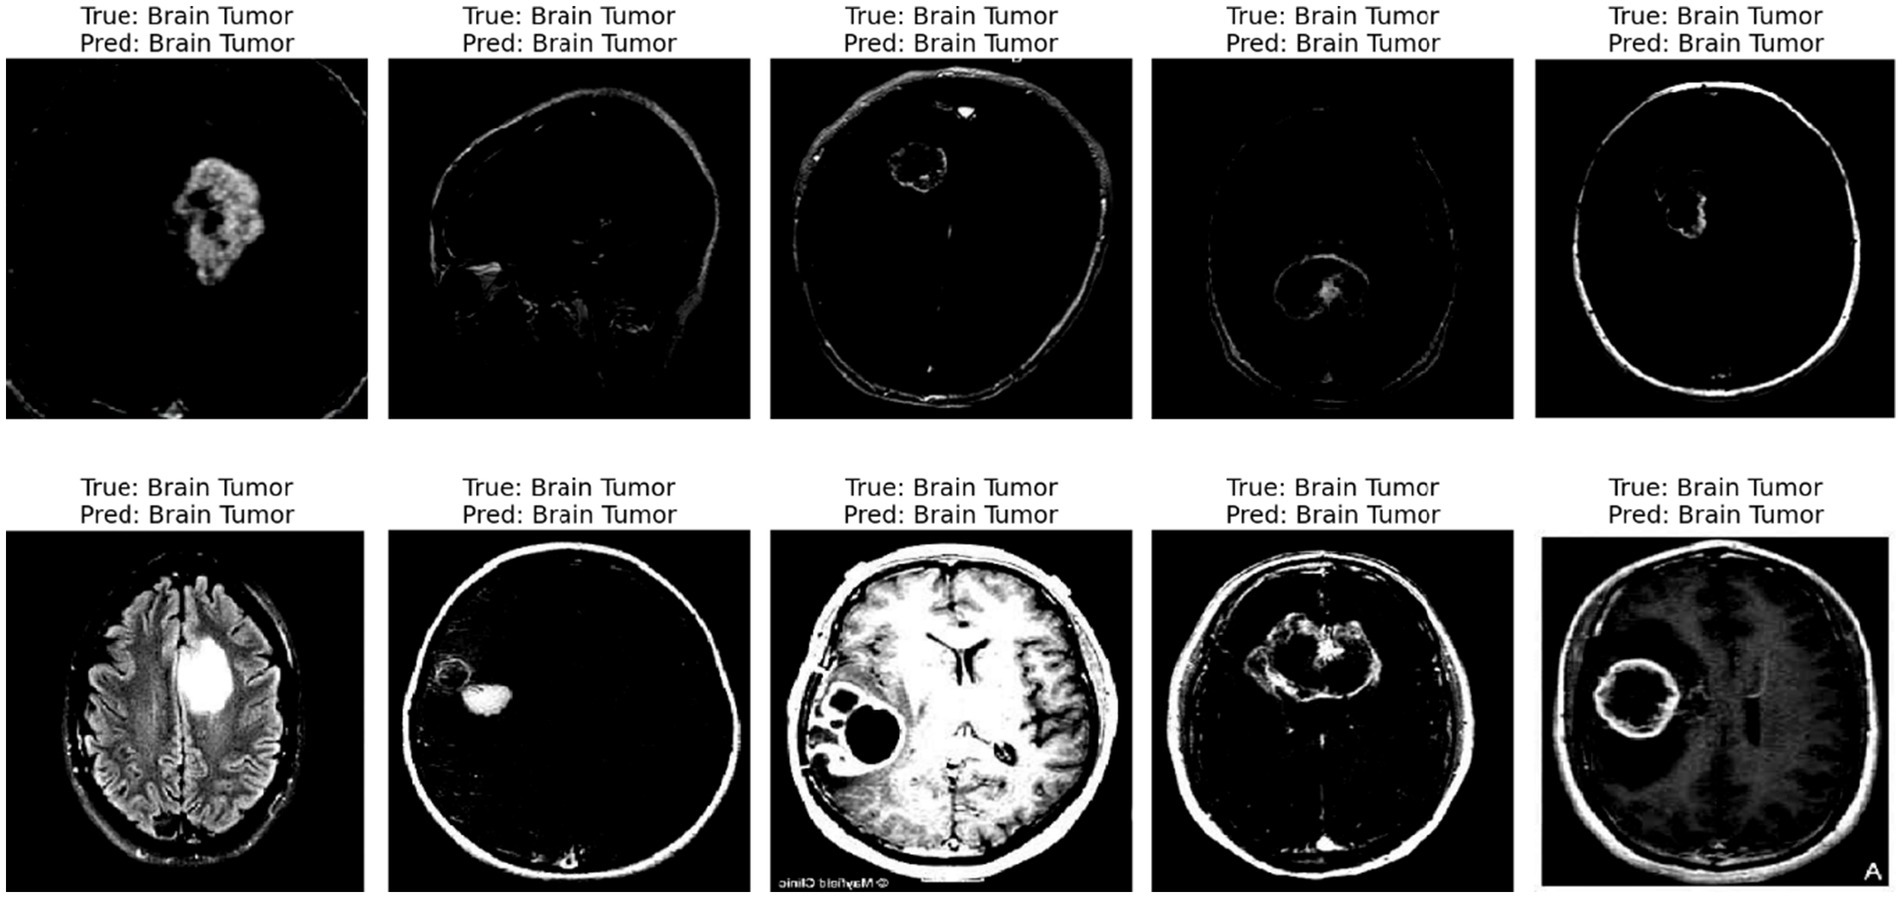

The displayed image shows a set of 10 brain scan samples, each labeled with both the ground truth (“True”) and the model’s classification result (“Pred”). In all five cases, the actual class is Brain Tumor, and the model has also correctly predicted Brain Tumor for each image. This visual representation provides qualitative evidence of the model’s effectiveness in correctly identifying brain tumor cases.

Each image appears to be a medical imaging scan—likely from MRI modalities in Figure 10—processed in grayscale. The tumors are visible as brighter or differently textured regions in the brain scans, suggesting that the model was able to detect distinguishing visual features associated with tumorous growths. The consistency in correct classification across different tumor appearances indicates that the model has likely learned to generalize the underlying patterns of tumor presence effectively.

Figure 10

Predicted result.